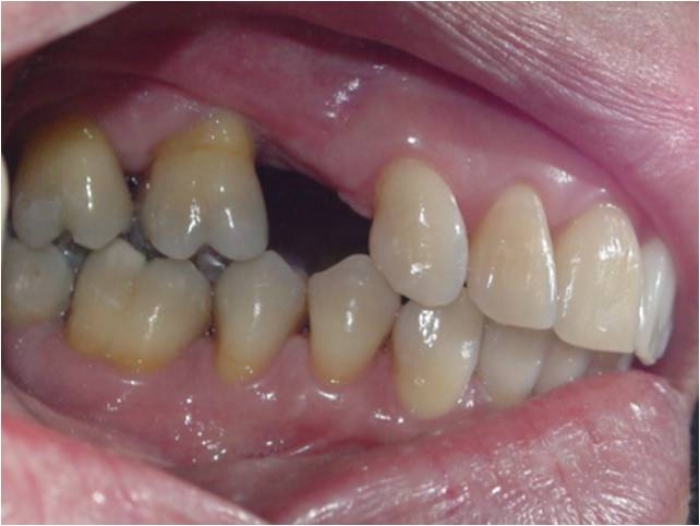

Raio X inicial, obsevando ausência de um pré molar superior à esquerda